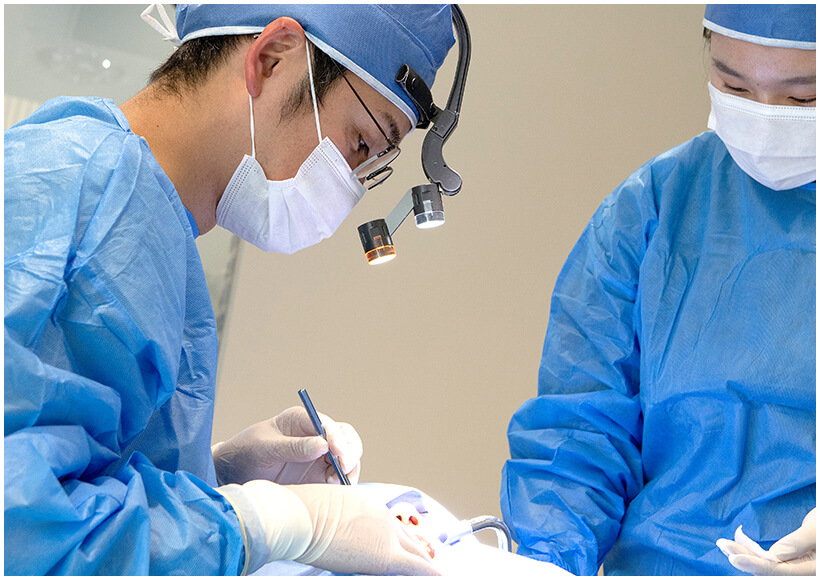

各治療に特化したドクターが連携し

チーム医療によるインプラント治療を行ないます

インプラント・歯周病の治療担当医が

責任をもって手術を行なうため、

安心して治療を受けていただけます

各治療の担当医が集まることで

より良い治療計画が可能になります